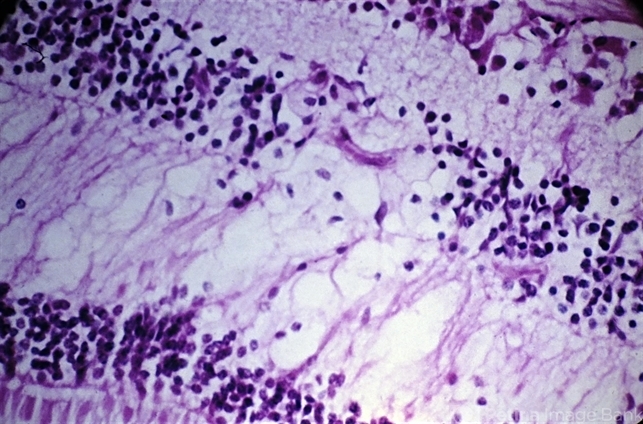

- retinal exudates, histiocytes, diabetic retinopathy

- Deep retinal exudate. There is accumulation of lipid-laden histiocytes in the outer plexiform and inner nuclear layers of the retina in the posterior pole area in diabetic retinopathy.